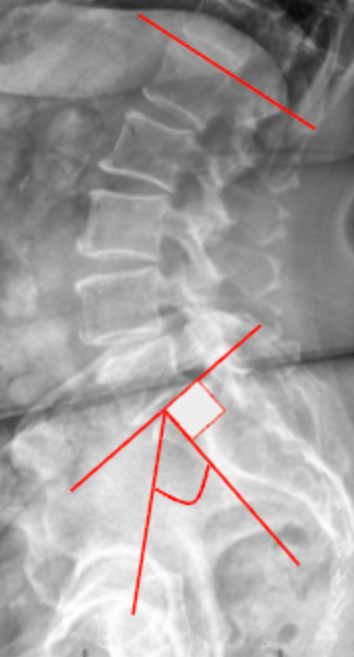

Slip Angle/Lumbosacral Kyphosis

Lumbosacral Angle (Ferguson’s Angle/Sacral Inclination)

Pelvic Incidence